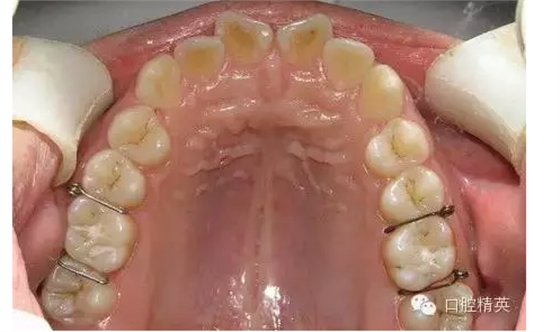

圖1

◆分牙簧各個口腔醫(yī)療器材商都有成品供應,但基本上是圖1形狀,即未激活狀態(tài),正確的使用方法是:在操作前用細絲鉗夾住簧圈處齦臂向內彎折,使齦臂末端靠近合臂,形成角度(圖2),分牙時撐開,插入鄰牙間,利用兩臂的剪切彈力,產生間隙。